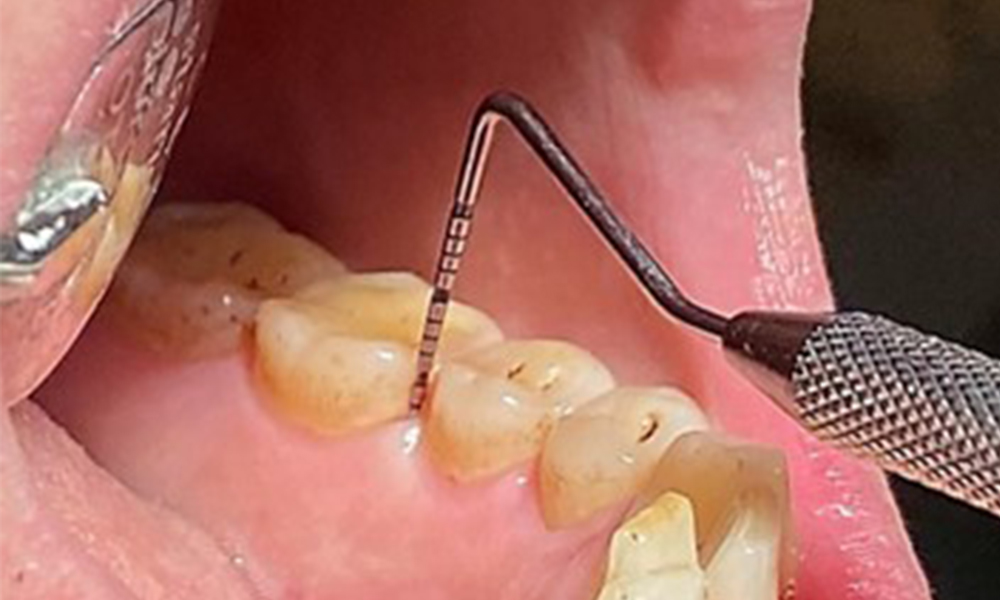

It is also necessary to check that the interdental brushes – used by this patient on a daily basis – are the correct size and encourage consistent use (Fig. 9). Good intraoral hygiene minimizes the risk of periodontitis from smoking.

Use of the interdental brushes in the area near 44/45

Fig. 9: Use of the interdental brushes in the area near 44/45, © Dr R. Krapf